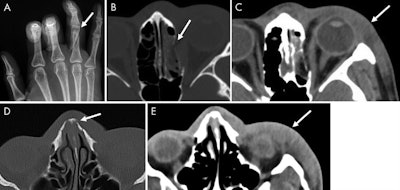

There were a number of imaging findings that could indicate intimate partner violence, according to the researchers. These included soft-tissue abnormalities, such as laceration and swelling; acute fractures; and ob/gyn findings such as intrauterine growth restriction, subchorionic hematoma, failed pregnancy, and retained products of conception. Patients who experienced violence were also more likely to have undergone more imaging studies, at a median of four exams per patient versus one exam per patient for the control group.